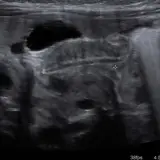

Over 2,100 interactive radiology cases, curated by radiologists for your level of training. Scroll, window, and view cases full screen — just like on PACS. Click linked findings in each writeup to jump straight to them on the image. Cases include sample reports, a focused discussion section, original illustrations, and videos.

Casos totalmente interactivos con las herramientas que esperaría de un PACS: scroll, ventana, zoom, pan, mediciones, ROI y modo de pantalla completa.

• Anotaciones enlazadas

Anotaciones extensas resaltan los hallazgos clave directamente sobre los casos. Haga clic en los hallazgos enlazados dentro de la descripción del caso para saltar a su ubicación exacta en el estudio.

Casos Interactivos

Desplace, arrastre, ajuste ventana y amplíe como en una estación PACS de trabajo

Aprenda con eficiencia gracias a hallazgos de imagen anotados e ilustraciones